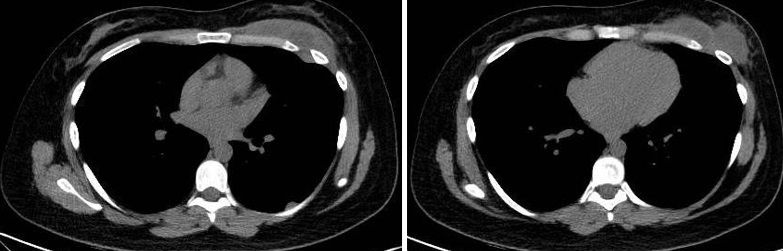

Paciente femenina de 26 años de edad, sin antecedentes patológicos de relevancia, sin dosis de vacuna BCG. Cursa con cuadro clínico de ocho meses de evolución, caracterizado por dolor en región pectoral izquierda intermitente, que se exacerba a la inspiración profunda. En el último mes se palpa masa indurada dolorosa a la palpación a nivel del cuadrante inferior interno de mama izquierda, motivo por el cual se realiza ecografía de partes blandas, donde se observa a nivel retropectoral en íntimo contacto con la parrilla costal imagen hipoecogénica de bordes delimitados, avascular al Doppler color por lo cual se solicita TC de tórax con EV. En ella se observa en topografía del cuarto espacio intercostal, imagen hipodensa con realce periférico tras la administración del contraste que desplaza por efecto de masa el parénquima pulmonar adyacente y se proyecta a la pared torácica anterolateral izquierda; mide 40 mm x 55 mm. Además, se visualiza otra imagen de similares características de base pleural en contacto con el octavo arco costal posterior izquierdo que mide 6 mm x 11 mm.

Cuatro meses posteriores a la PAAF la paciente refiere persistencia de dolor y aumento de tamaño de la masa asociado a eritema en región mamaria, por lo cual se realiza TC de tórax con contraste EV donde se observa imagen hipodensa ya conocida, con realce periférico tras la administración de contraste, con aumento de tamaño y bordes lobulados.

Hallazgos imagenológicos

Los estudios de imagen, especialmente la radiografía de tórax y la tomografía computarizada (TC), tienen un papel importante en el diagnóstico de la tuberculosis pleural, ya que la radiografía de tórax nos permite identificar el derrame pleural, la afectación unilateral y posibles consolidaciones pulmonares. En fases avanzadas, también puede mostrar engrosamiento pleural o secuelas fibrosas.

La tomografía computarizada proporciona información más detallada sobre el compromiso extrapulmonar, revelando ganglios linfáticos mediastinales aumentados o nódulos subpleurales que sugieren focos de infección activa.